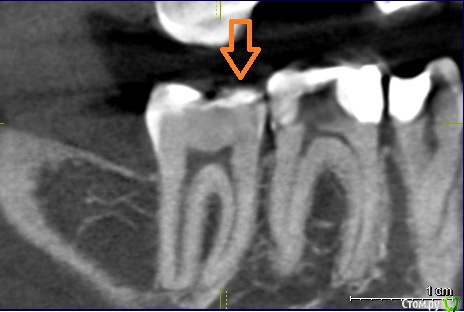

Прилагаю фото рентгена зуба. (сделан примерно полгода назад еще до перестановки пломбы).

Стрелкой помечено место, куда больно надавливать. Пломба на всю жевательную поверхность зуба.